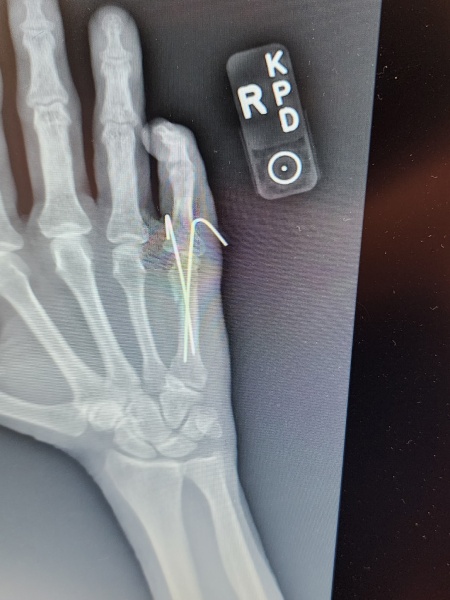

Travis | Support Mgr. Close enough. I punched my bedroom wall in frustration. And in fact this is called a boxer's fracture. I just happened to hit a stud, which I knew immediately when I saw there was no hole in the drywall. Then I saw the bump on my hand and I could feel the bones moving back and forth when I squeezed them with my left hand

Doc put pins in the bones:

Just had them yanked out today. Not funDUCI HEXA YIWA 0721